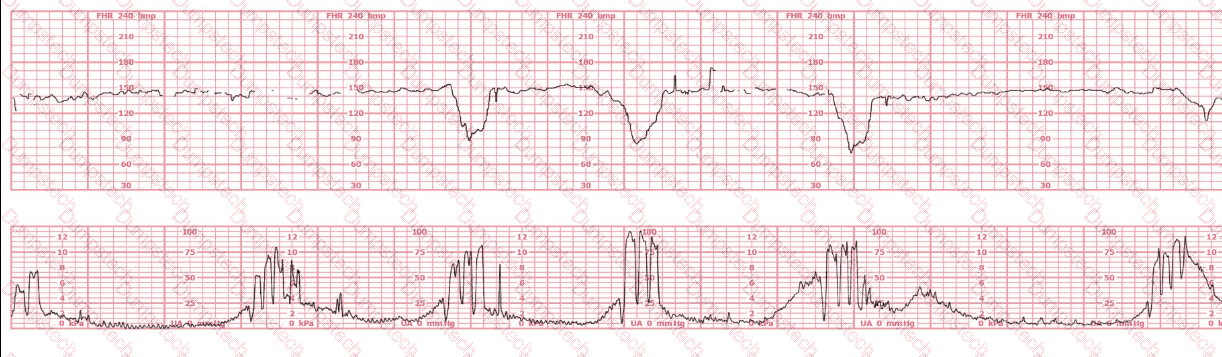

A woman in labor has been pushing for 4 hours. For the last 2 hours, there have been recurrent variable decelerations. Variability has evolved from moderate to minimal. Cervical exam is 10/100%/+2, fetal head OP. There has been no fetal descent for the last 45 minutes. Based on the tracing shown, the most reasonable approach is